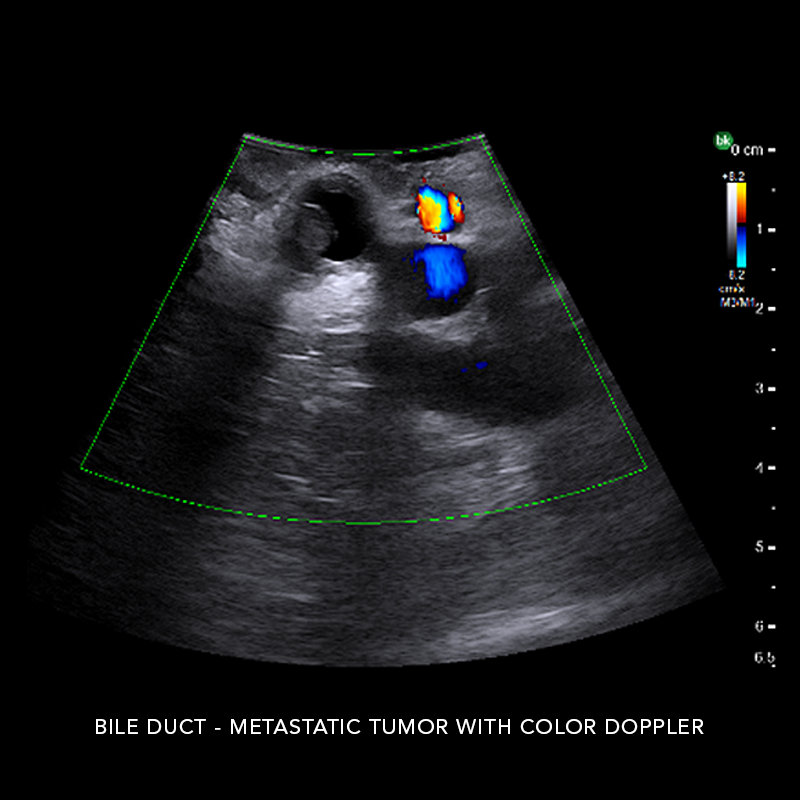

Hepatobiliary Surgery

Reach critical information and compensate for no haptic feedback with active imaging

Intraoperative ultrasound can assist in identifying 10-25% more hepatic lesions than with preoperative imaging alone.* Use intraoperative ultrasound (iUS) to support liver resections, distal pancreatectomies, and more. iUS helps to adapt surgical plans, assess progress, and perform organ-sparing procedures. The active imaging provides real-time information to understand complex anatomical variations, tumor locations, and invasion of vasculature, as well as help define an adequate margin of rection. At the end of the procedure, active imaging can provide certainty and help confirm results.